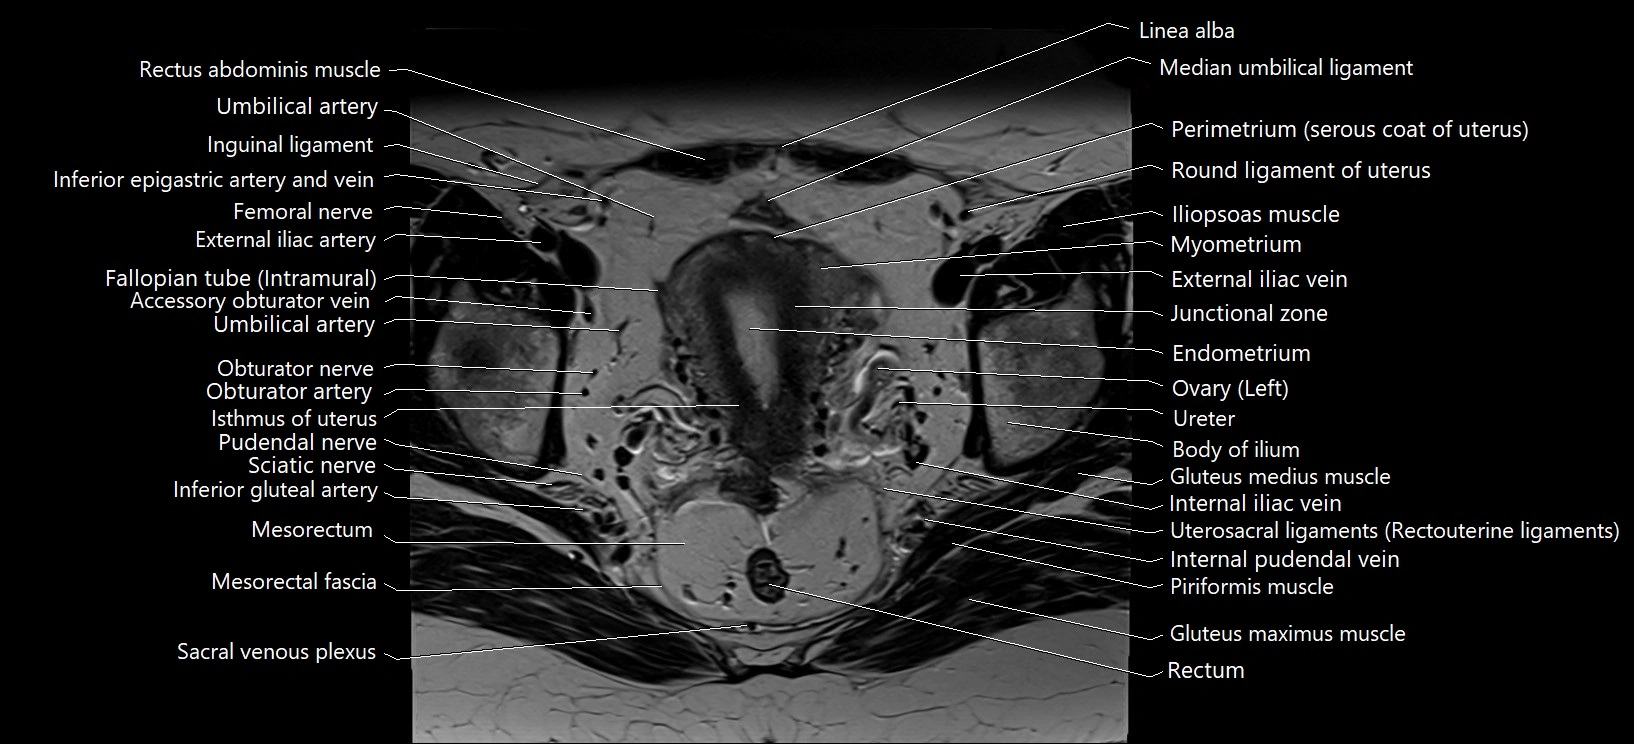

- Broad ligament of uterus

- Endometrium of uterus

- External iliac artery

- External iliac vein

- Fallopian tube

- Femoral nerve

- Inguinal ligament

- Internal iliac vein

- Internal pudendal vein

- Isthmus of uterus

- Junctional zone of uterus

- Linea alba

- Median umbilical ligament

- Mesorectal fascia

- Myometrium of uterus

- Obturator externus muscle

- Obturator nerve

- Perimetrium of uterus

- Piriformis muscle

- Pudendal nerve

- Round ligament of uterus

- Sciatic nerve

- Uterosacral ligament